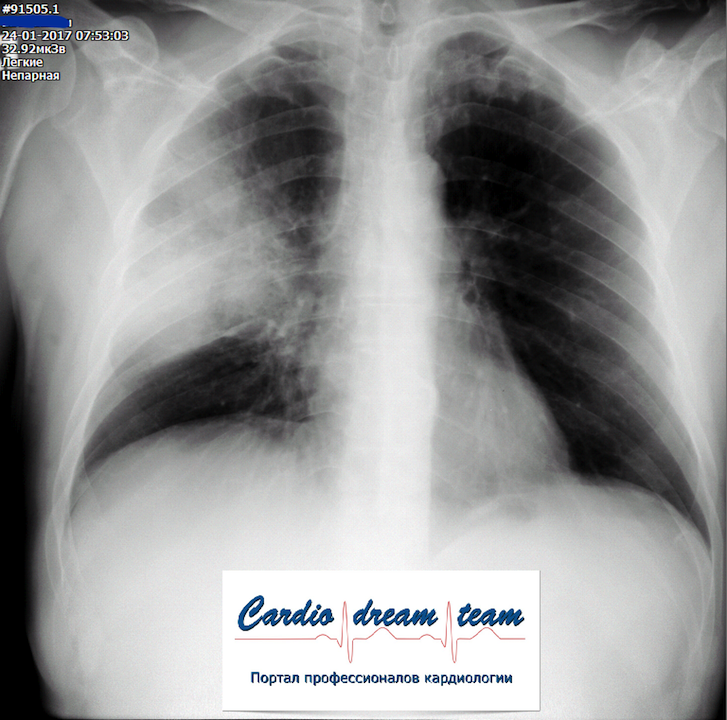

Долевая пневмония справа

Обсуждалось в Госпитале Ослабленных Сердец